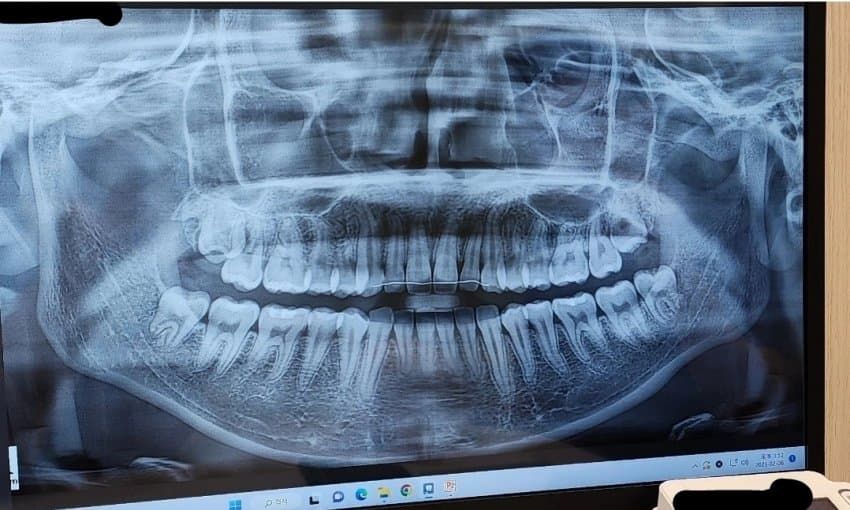

저 치근 짧은 편인가요..?...?

치아교정을 어릴때 했었는데 자라면서 다시 개방교합이 되어서 재교정을 하고싶은데, 치근 짧은편인가요?

재교정 가능할지 궁금합니다..

교정하면 치근흡수가 어느정도 되는건 흔한 부작용입니다 사진상 치아 기울어진 각도 때문에 왜곡이 있을 수 있다는 점도 감안되아야 하나 짧아보이긴 합니다 다만 치근이 짧다고 아예 재교정을 못하고 그런건 아닙니다

다른부분은 괜찮지만 아래 앞니나 윗니의 뿌리가 정상적인 치아보다 짧은거 같습니다. 크게 문제가 잇는건 아니니 관리만 잘하면될것같습니다.

아래 앞니가 부분적으로 치근이 조금 짧아보이기는 하지만 재교정은 가능할 것으로 보입니다.

이정도면 정상적인 치근 사이즈라고 보면 됩니다. 재교정 필요하다면 하시면 됩니다. 윗니 앞니 안쪽에는 교정 유지장치가 부착되어 있습니다.